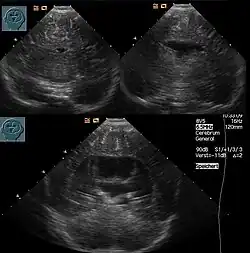

- lobäre Holoprosencephalie (Trennung ist größtenteils erfolgt, kompletter Interhemisphärenspalt, zwei Seitenventrikel mit rudimentärer Verbindung)[13]

Die Diagnose kann vorgeburtlich im Rahmen von Pränataldiagnostik durch insbesondere Feinultraschalluntersuchungen im zweiten Trimenon, teils aber auch schon früher, gestellt werden. Während die Feststellung der alobären und der semilobären Form oft recht einfach ist, ist die der lobären Holoprosencephalie komplizierter.

Nachgeburtlich sind die Schnittbildverfahren Sonographie und Magnetresonanztomographie Methoden der Wahl.[19]